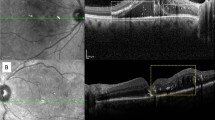

Figure 5A,B shows examples of normal and ERM OCT images with Grad-CAM visualization effect overlaid. Regions highlighted with warmer colors represent those areas more important for the final class determination. The ERM region of interest (ROI) was captured precisely and results are compatible with judgement of the retinal specialist.